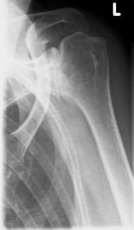

Abbildung2Abbildung1

left: X-ray image of an omarthrosis

right: X-ray of a healthy shoulder joint

X-rays can be used to reliably diagnose the extent of joint wear. In the case of severe osteoarthritis, for example, the joint space and the formation of jagged edges (osteophytes) can be detected. If additional damage to the tendons of the shoulder (rotator cuff) is suspected, ultrasound examination (sonography) or magnetic resonance imaging (MRI) can help clarify the situation.